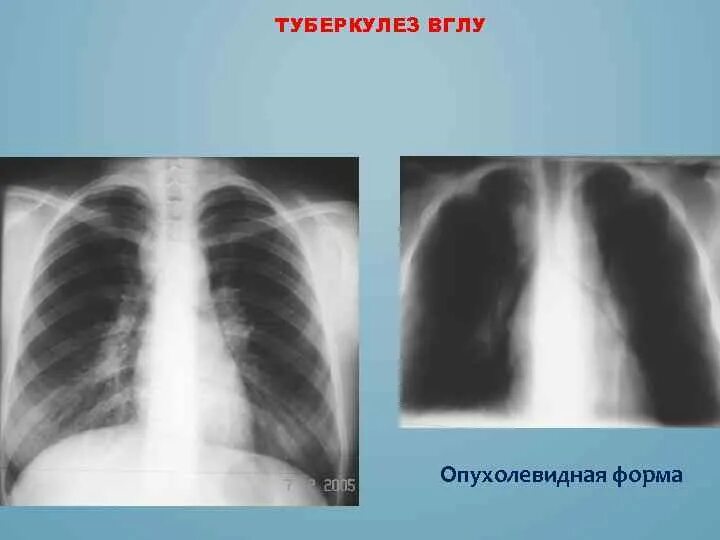

Бронхоаденит это